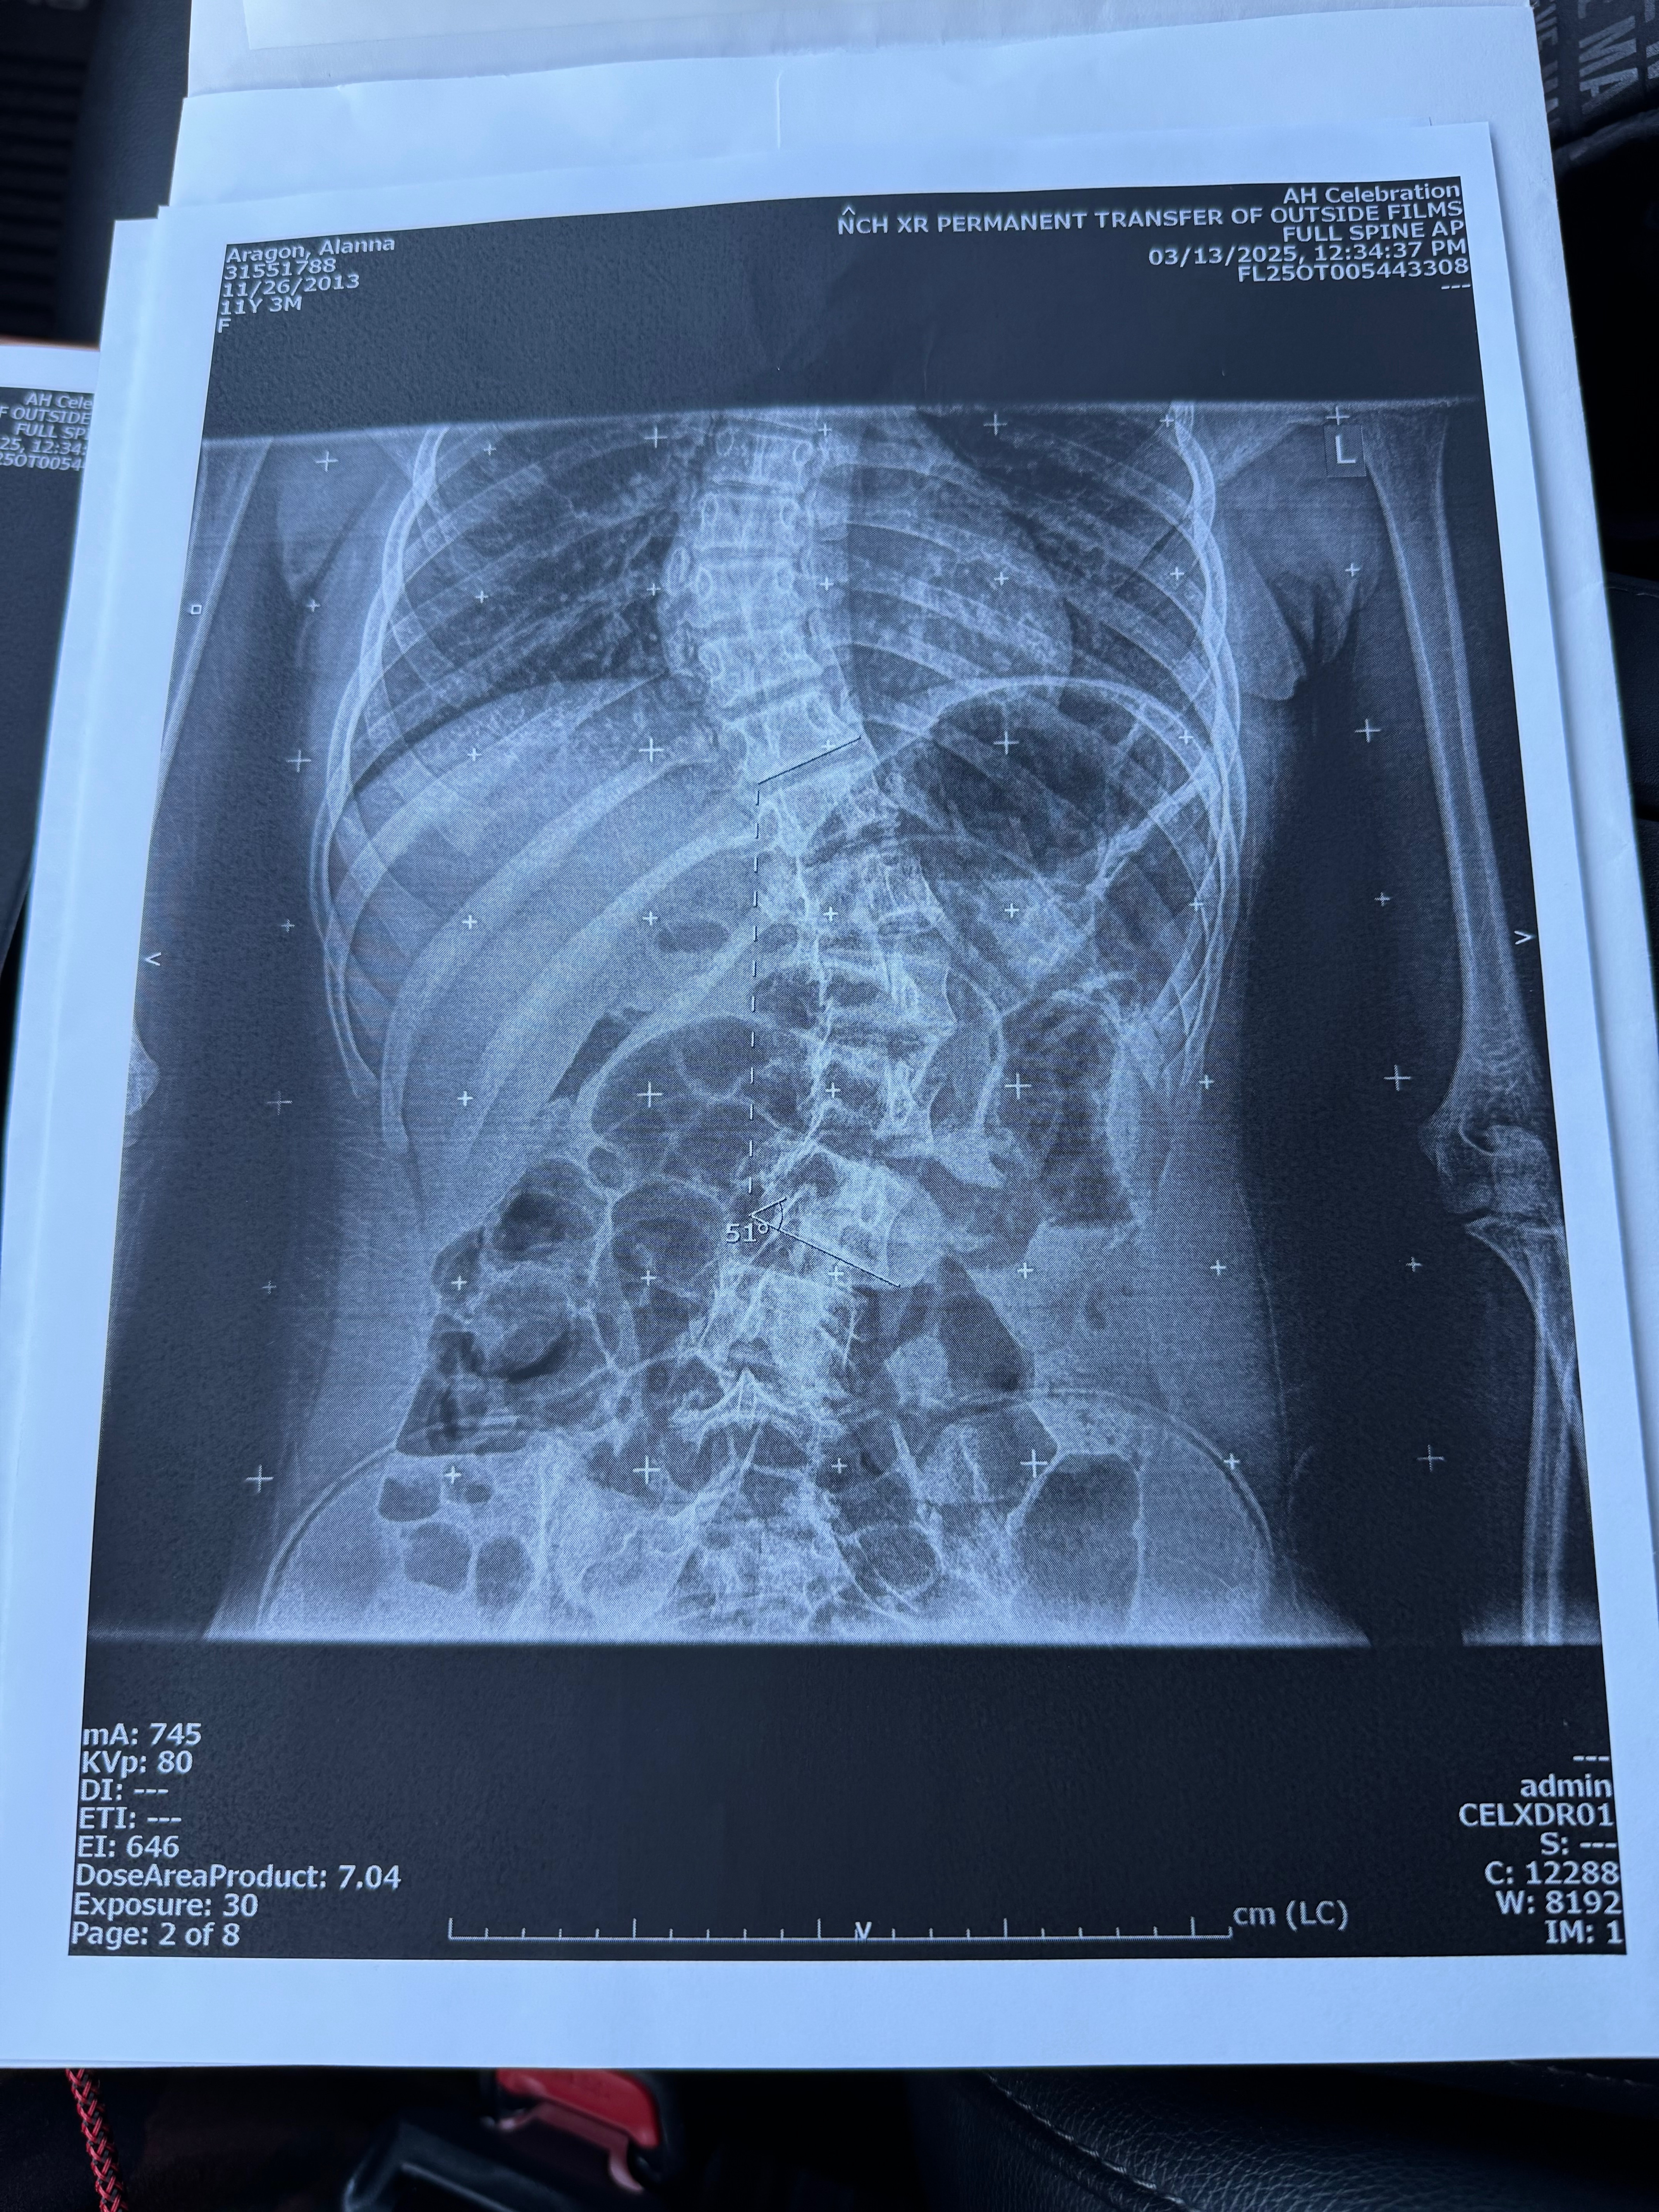

On May 14, she had an appointment with the orthopedic because of her scoliosis condition. That day, they gave me the news that she needs surgery. Her condition is severe.